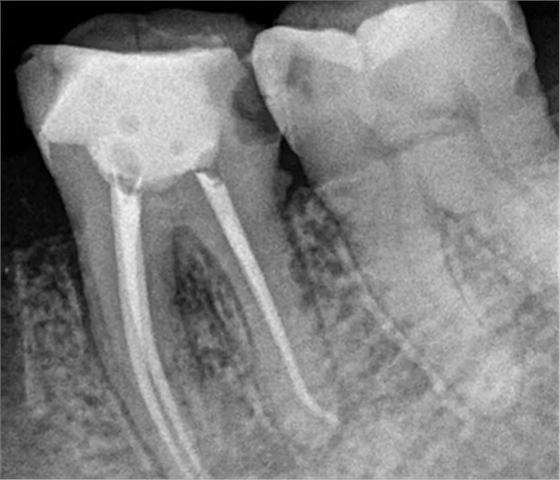

根管治療術(shù)又稱牙髓治療,是牙醫(yī)學(xué)中治療牙髓壞死和牙根感染的一種手術(shù)。該手術(shù)保留了牙齒,先是揭開髓室,頂敞開通路,用拔髓針拔除感染的牙髓。在用擴(kuò)挫針擴(kuò)凈根管壁,之后在根管內(nèi)封消炎藥,最后再用牙膠尖充填,手術(shù)繁瑣,一般要2-4次就診才能完成。隨著技術(shù)和材料的進(jìn)步,活髓牙一次性根管治療術(shù),也在臨床應(yīng)用。